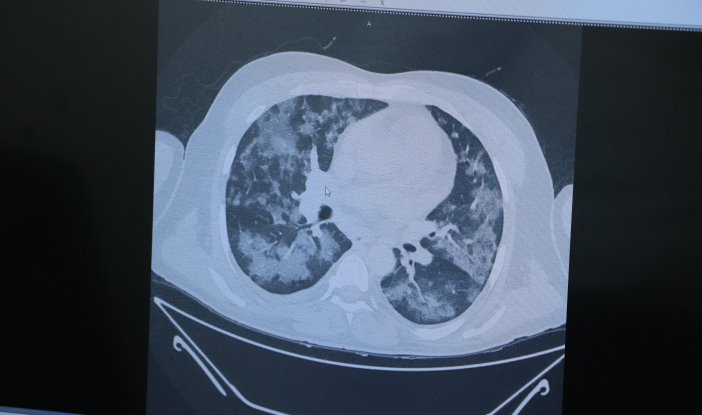

Tedavi altındaki 5 kişinin akciğerlerini inceleyen Prof. Dr. Özkaya, "Hâlâ bu hastalığa inanmayanlar olabilir. Bu hastalığın yapay, suni bir medya haberi olduğu söyleniyor. Size şu an 5 hasta örneği göstereceğim. 5’i de şu an yatıyor ve yaşam mücadelesi veriyor. Okulda bir yarışma düzenlendiğini düşünün, tüm Türkiye’de okullar arası bir yarışma yapılıyor ve yarışmada bir resim yapmanızı istiyorlar. Tüm Türkiye’deki bütün okullardaki öğrenciler birbirinden bağımsız olarak aynı resmi yapıp getiriyorlar. Böyle bir şey mümkün mü? 58 yaşında bir hastamız, akciğerinde yaygın Covid-19 lekesi. Birbirinden bağımsız ayrı insanlar. Yine aynı tabloyla gelen başka bir hasta ve yine aynı tabloyla yatan başka bir hasta. Bu hastaların hepsi şu an yaşam mücadelesi veriyor ve büyük oranda tedavi edebildiğimiz hasta grupları. Böyle bir tabloyu biz bugüne kadar hiç görmedik. Bugüne kadar yaşayan en yaşlı doktorlar bile akciğerleri böyle etkileyen bir bulaş hastalığı görmedi. Bu bir gerçektir, bu bir yaşadığımız hayat tecrübesidir. Lütfen daha duyarlı olalım" ifadelerini kullandı.